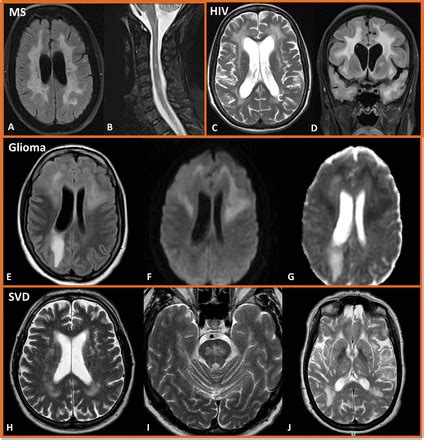

Understand the causes, symptoms, and treatment options for periventricular white matter disease. This comprehensive guide explores how this condition affects brain health, its link to small vessel disease and vascular dementia, and the latest management strategies to improve neurological outcomes. Learn how to identify early warning signs and protect your cognitive function through expert medical insights.

Read full article: Periventricular White Matter Disease